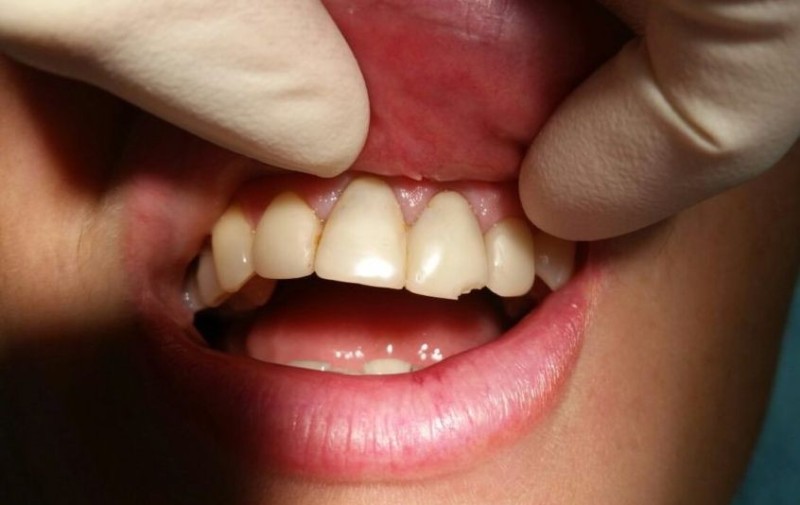

Писарская Елена Николаевна: портфолио (2)